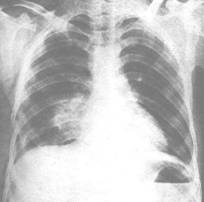

(3)胸部X线检查:慢阻肺早期X线胸片可无明显变化,以后出现肺纹理增多和紊乱等非特征性改变;主要X线征象为肺过度充气:肺容积增大,胸腔前后径增长,肋骨走向变平,肺野透亮度增高,横膈位置低平,心脏悬垂狭长,有时可见肺大疱形成。

COPD患者影像学改变